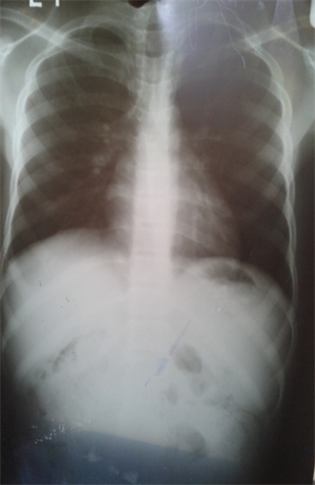

- Chest X-Ray (CXR)―mild hilar lymphadenopathy (Figure 5)

Figure 5. Chest X-Ray with mild hilar lymphadenopathy Reproduced with permission.

Making the diagnosis of TB in our index patient was not easy because we did not isolate mycobacterium tuberculosis and Ziehl Nielsen test was negative. However, the chronicity of his cough, a history of haemoptysis, weight loss, and positive mantoux test increased our suspicion of TB. Although the hilar lymphadenopathy on his CXR was not very prominent, the CXR film did not appear typically normal. Again, the viral warts were a sign of immunosuppression despite the fact that he was HIV negative. All these increased our suspicion for EPTB.